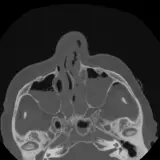

PACS์—์„œ ๊ธฐ๋Œ€ํ•  ์ˆ˜ ์žˆ๋Š” ๋ชจ๋“  ๋„๊ตฌ๋ฅผ ๊ฐ–์ถ˜ ์™„์ „ํ•œ ์ธํ„ฐ๋ž™ํ‹ฐ๋ธŒ ์ฆ๋ก€ — ์Šคํฌ๋กค, ์œˆ๋„์šฐ ์กฐ์ ˆ, ํ™•๋Œ€/์ถ•์†Œ, ํŒจ๋‹, ๊ณ„์ธก, ROI, ์ „์ฒด ํ™”๋ฉด ๋ชจ๋“œ๊นŒ์ง€ ์ง€์›ํ•ฉ๋‹ˆ๋‹ค.

์‹ค์ œ PACS ์›Œํฌ์Šคํ…Œ์ด์…˜์ฒ˜๋Ÿผ ์Šคํฌ๋กค, ํŒจ๋‹, ์œˆ๋„์šฐ ์กฐ์ ˆ, ํ™•๋Œ€/์ถ•์†Œ๊ฐ€ ๊ฐ€๋Šฅํ•ฉ๋‹ˆ๋‹ค